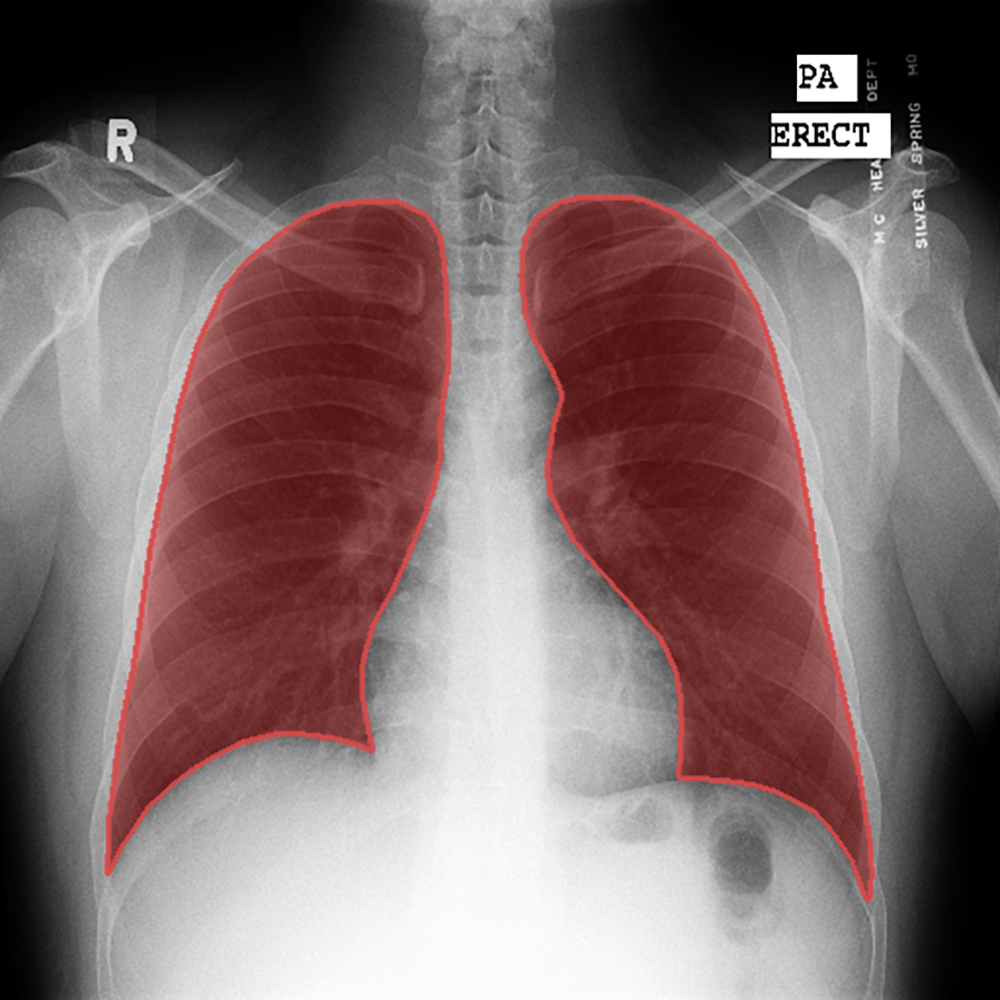

Introduction: We present a collection of lung segmentation models designed for accurate analysis of chest X-ray (CXR) images. These models have undergone rigorous training, validation, hyperparameter tuning, and testing on a diverse dataset consisting of CXRs from three publicly available sources: the Darwin, Montgomery, and Shenzhen datasets.

Dataset Description: The dataset includes CXRs from patients diagnosed with various respiratory diseases, including COVID-19, pneumonia, and tuberculosis. While these conditions differ in nature and disease patterns, we intentionally included them in the training data to improve the ability of the models to generalize across a range of pathologies. The dataset is summarized in Table 1 and publicly available at https://data.mendeley.com/datasets/8gf9vpkhgy/2.

Model Comparison: After a thorough evaluation, DeepLabV3+ emerged as our top choice. It exhibited exceptional performance with a DSCtest score of 0.963, while maintaining computational efficiency with a total of 7.4 million parameters and 2.2 billion MACs. This combination of high performance and computational efficiency solidified its position as the optimal model for our lung segmentation task.

Segmentation example - Shenzhen.png